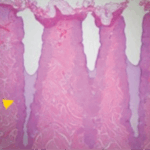

Treated skin histology

Two days post-treatment – Skin is healing on the surface and creating new dermal collagen. This will continue for up to six months. The improved skin quality will make for a more youthful appearance.